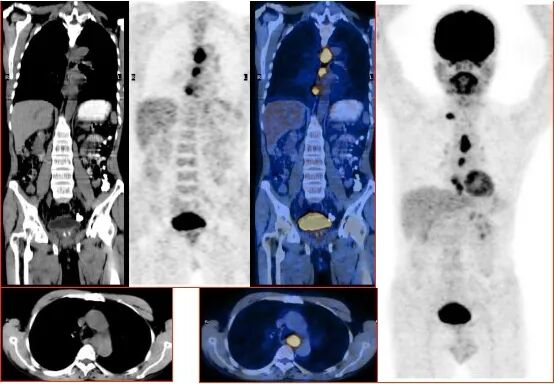

胃癌全身广泛转移

图片

多起源食管癌